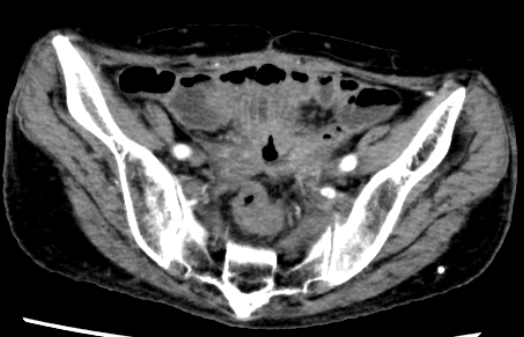

79岁的罗奶奶,20年前进行了卵巢癌根治术,术后1年出现阴道残端复发又进行了盆腔放疗。7个月前复查时PET-CT发现盆腔肿物怀疑为卵巢癌复发,在外院进行了开腹探查,术中见腹腔严重粘连,行小肠部分切除术及回肠造口术。不幸中的万幸,盆腔肿物病理结果为炎性组织,并非肿瘤复发。但罗奶奶并未充分评估身体状况,回肠造口还纳术后出现了严重的切口感染,再使用各级抗生素后又出现了顽固性的腹泻,更不幸的是出现了直肠阴道瘘,粪便改道持续从阴道流出给患者带来了巨大的痛苦。一系列地打击使患者体重从60公斤下降至40公斤,营养状况极差,并且出现多重耐药。

所幸患者家属经他人介绍,了解到了浙江省中医院胃肠外科陈贵平主任团队,随即到省中医院住院治疗。陈主任与患者及家属充分沟通,全面了解患者情况后,立即组织全院的讨论,与各科室专家充分交流后制定周全的治疗方案。患者经过充分的肠内外营养支持,康复锻炼恢复肌肉功能,体重上升了3公斤后,陈主任果断决定进行手术治疗。术中见腹腔内广泛的粘连,尤其是放疗导致的盆腔组织粘连,十分致密。经过陈主任不懈的努力,成功分离出直肠和阴道的瘘口,将瘘口切除后,重新吻合直肠和乙状结肠,并进行回肠预防性的造口。目前罗奶奶已恢复饮食,并且解决了阴道流粪的痛苦。